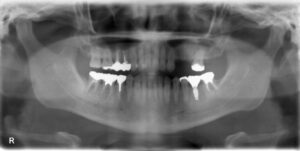

上顎小臼歯2本欠損症例

BEFORE AFTER 47歳男性/上2本欠損/インプラント埋込手術 【治療内容】 左上第一小臼歯、第二小臼歯を数年前…